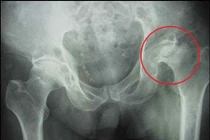

(khoahocdoisong.vn) - Hoại tử vô khuẩn chỏm xương đùi hay còn gọi là hoại tử vô mạch (Avascular Necrosis) chỏm xương đùi là bệnh có tổn thương hoại tử tế bào xương và tủy xương do thiếu máu nuôi trên chỏm xương đùi.